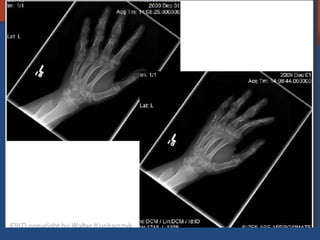

Olier disease

• Enchondromatosis

• No hereditary sporadic skeletal disorder

• Ddx

– Maffucci = plus hemangioma

– Metachondromatosis = plus osteochondromas